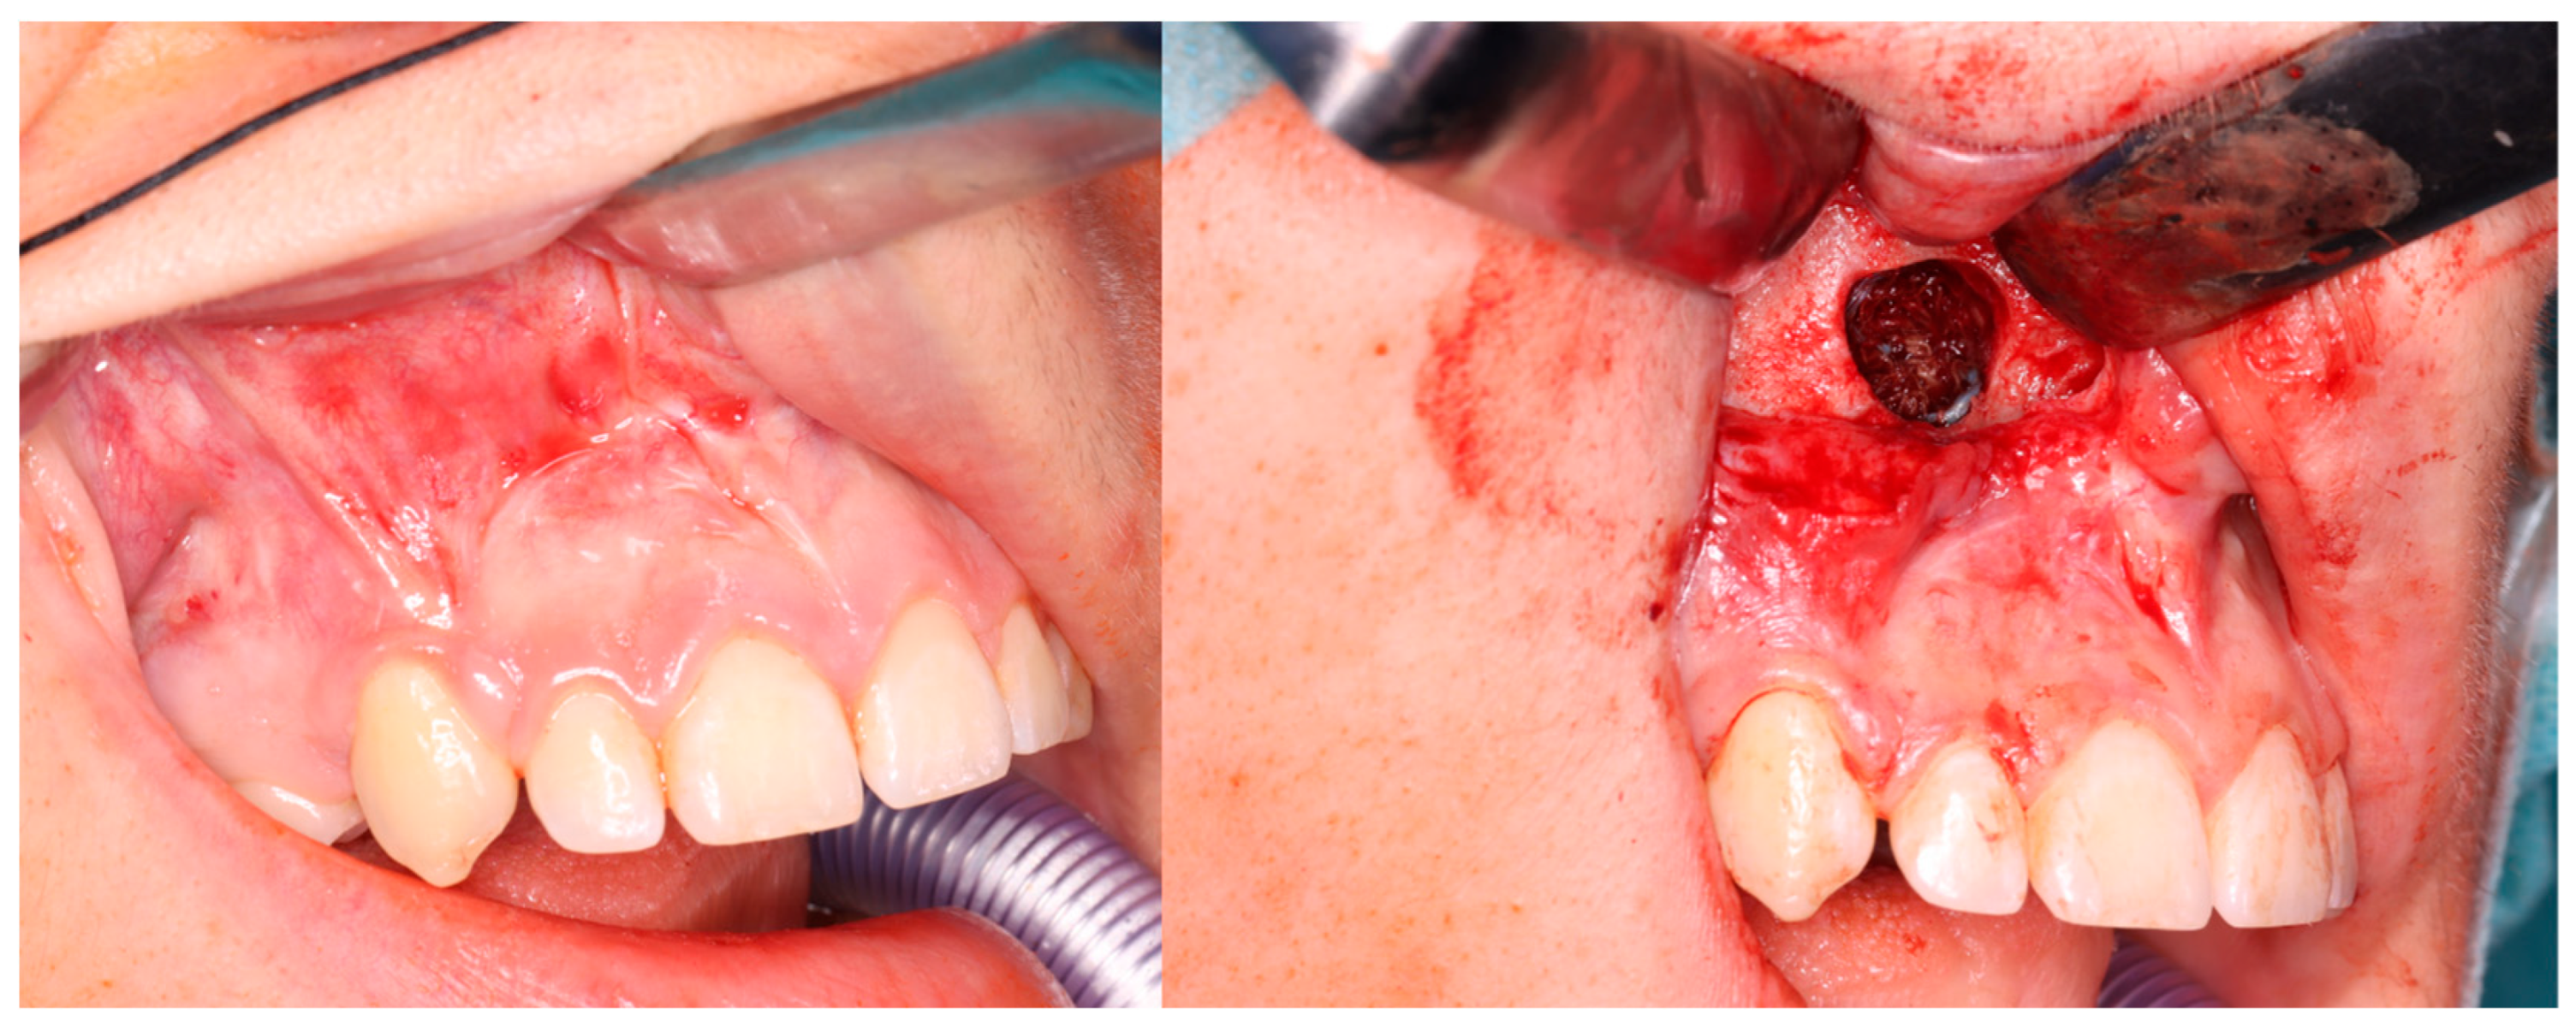

2. Materials and Methods

3.2. Injections